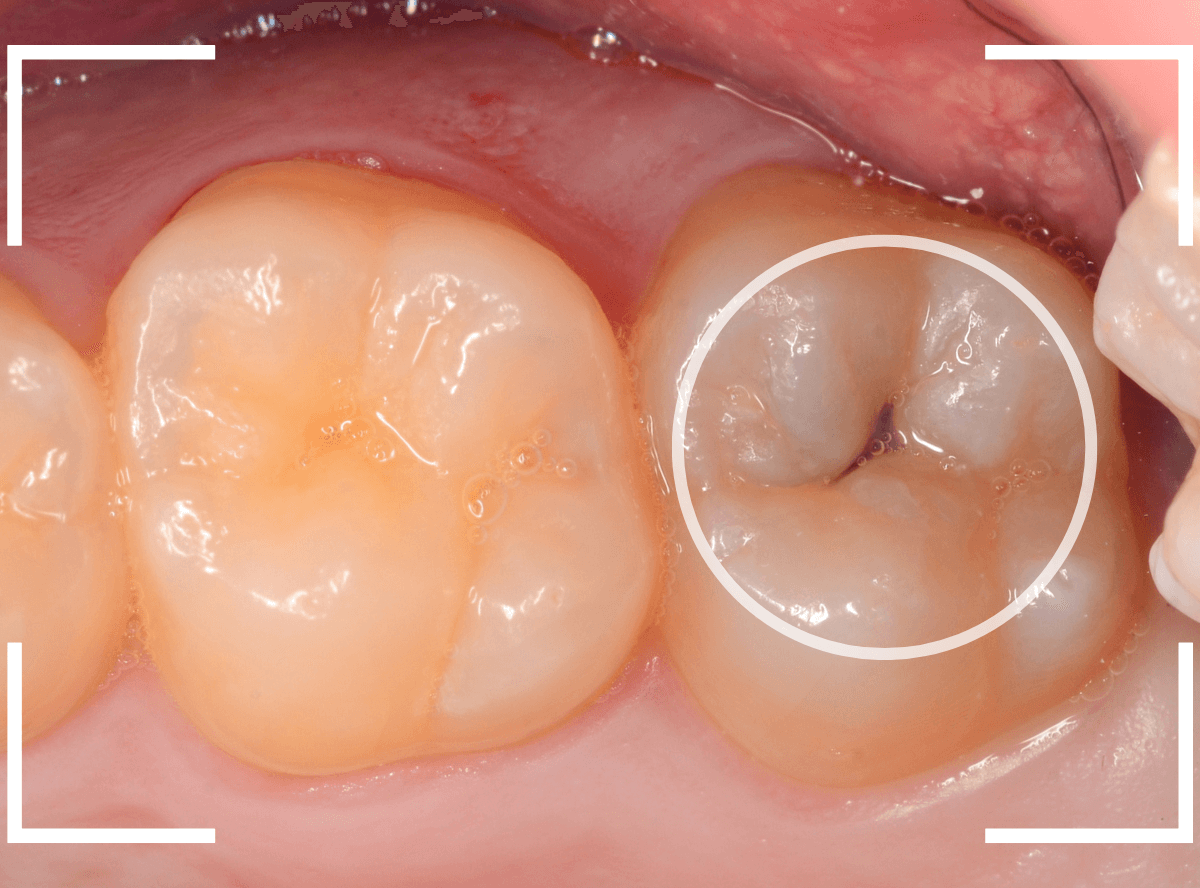

Case.2 レントゲンで判別しづらい、小窩裂溝う蝕

今回は、レントゲン写真で判別しづらい、小窩裂溝う蝕です。

写真では、2本の歯とも、歯の溝に虫歯が出来ているのが確認できます。

レントゲン写真で確認します。

〇部が虫歯の部分です。

左側の歯はうっすらと黒い影が見えますが、わかりづらい写り方です。